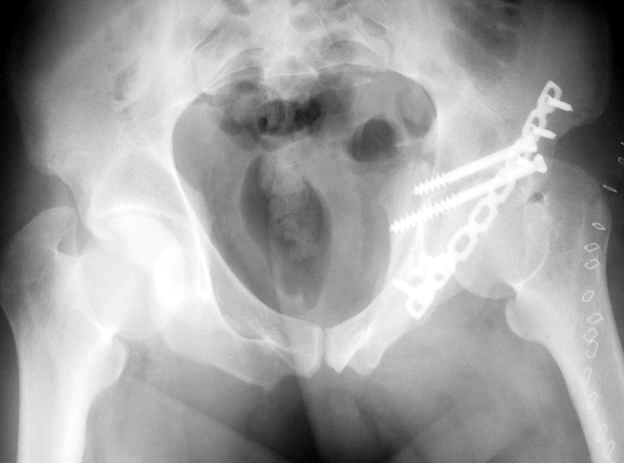

Не дождавшись советов, в понедельник прооперировал больного, заняло времени..., но все сделал в один этап: сначала фиксировал ипсилатеральный перелом бедра и шейки реконструктивным гвоздем Smith&Nephews, потом из расширенного илеофеморального доступа фиксировал перелом крыла подвздошной кости тягловым винтом, нейтрализующей пластиной заднюю колонну, и тягловыми винтами 3,5 мм переднюю колонну.

Несмотря на расширенный доступ, особой кровопотери не было, перелил только одну дозу эр.массы и на утро Нв- 10.5 и как ни странно больной не жалуется на сильные боли и стопа не *висит*, хотя при интраоперационной ревизии седалищного нерва обширная гематома в периневральной оболочке.

К сожалению, набора для ретроградного или антеградного реконструктивного штифтования в операционной нет, поэтому доставка заняла н-ное время. Вопрос, который возник у меня- по поводу оптимальной тактики хирургии: вся фиксация в один этап из расширенного доступа или последовательно сначала бедро и позже реконструкция впадины, комбинированный доступ к впадине отдельно к передней и задней колоннам или из расширенного илеофеморального одного доступа. Все-таки решил остановиться на одноэтапном подходе и спустя 5 дней (как раз и наборы привезли) из расширенного илеофеморального доступа сначала фиксировал реконструктивным штифтом Smith&Nephews бедро и

шейку (благо перелом шейки 2 типа -относительно стабильный) затем фрагмент крыла подвздошной кости Lag screw, далее пластина на заднюю колонну и винты в переднюю колонну.(с размерами и направлением винтов ошибка вышла:-((, но интраоперационно у меня была полная уверенность , что винты *ушли* в лонную кость).

Еще раз спасибо за комментарии и готовность помочь с имплантами. Постоп картинки в приложении,